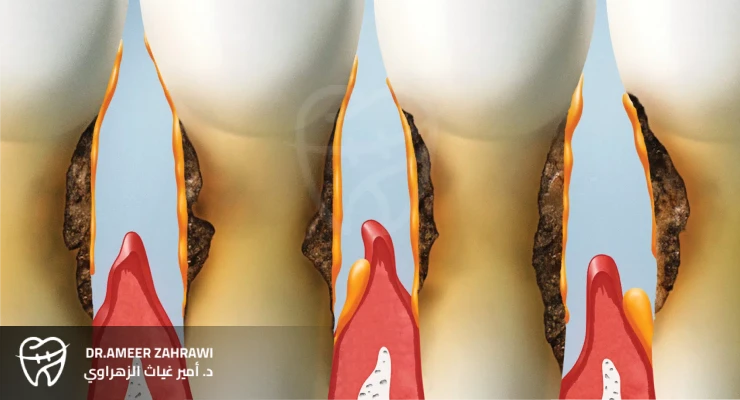

Your mouth is home to many bacterial colonies. Oral bacteria constantly adhere to your teeth and form a sticky film known as plaque. That’s why it’s important to brush your teeth regularly to prevent plaque buildup. When plaque is not removed for a prolonged period, it can lead to gingivitis and periodontitis.If plaque is not regularly removed from the tooth surfaces, it starts to accumulate below the gumline and attach to the teeth in areas that are impossible to clean with a toothbrush or dental floss. Once plaque begins to build up in an area of the mouth where it cannot be easily removed, the bacterial colonies multiply and harden into a substance called tartar (calculus). When both plaque and tartar are present beneath the gums, bacteria multiply rapidly and begin to damage the soft tissues surrounding the teeth.Factors that can contribute to the development of gum disease include:

If gingivitis is left untreated, it can progress to periodontitis. Periodontitis is an inflammatory condition around the tooth that damages the surrounding bone and the fibers (periodontal ligament) that hold the teeth in place. There are several types of periodontitis:

This is the most common type of periodontitis. It is characterized by ongoing inflammation and the gradual loss of attachment between the tooth and its supporting tissues.

This form progresses rapidly and is more commonly seen in younger individuals.

Necrotizing Periodontal Disease

This is a severe infection characterized by necrosis (death) of the gum tissue, periodontal ligament, and supporting bone.

Advanced Periodontitis

In the advanced stages of periodontitis, the bone and supporting fibers that keep the teeth in place are severely destroyed. This can lead to tooth mobility and eventually tooth loss, and may require more complex treatments such as periodontal surgery or dental implants.